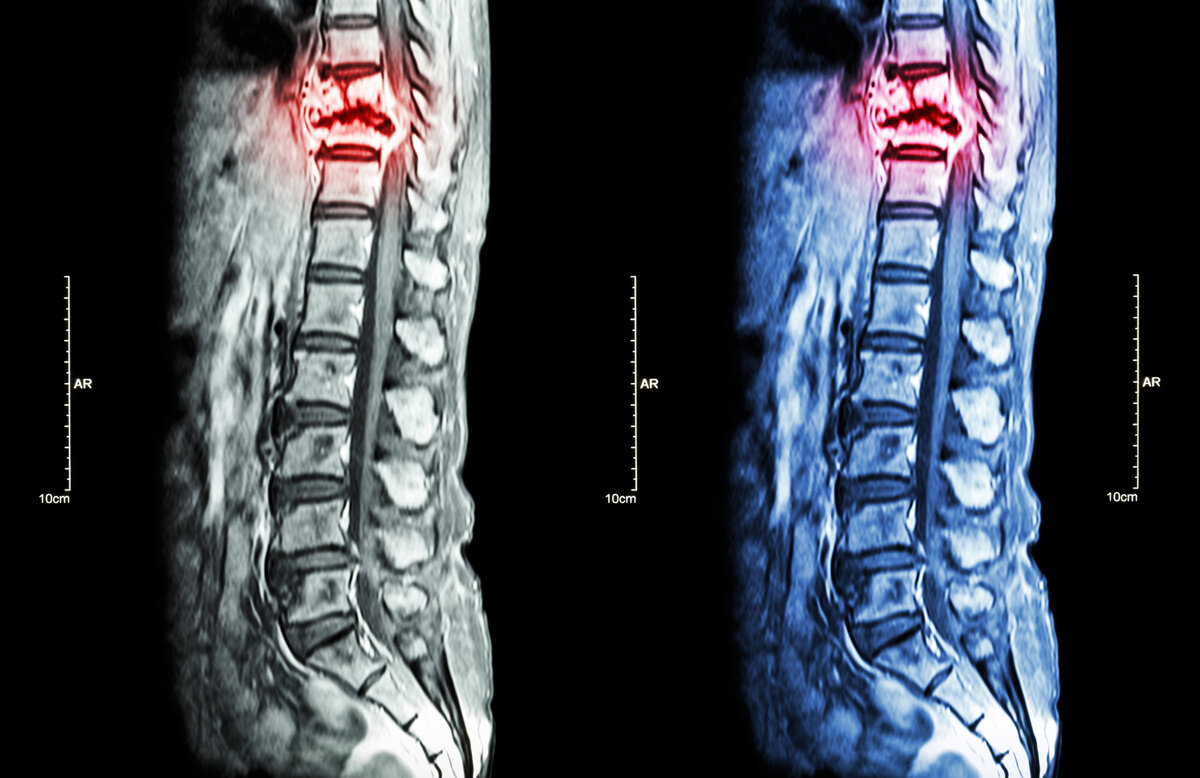

Чаще всего костные метастазы обнаруживаются в позвоночнике. Другие частые места локализации: кости таза, бедро, плечевая кость, ребра, череп.

Позвоночник – самое часто место локализации костных метастазов. Опухолевые очаги могут приводить к переломам позвонков.

Патологические переломы при метастазах в костях происходят, когда нет каких-либо сильных нагрузок, во время привычных повседневных действий. При этом возникает сильная боль, движения в поврежденной части тела становятся невозможны. При патологическом переломе позвонков может произойти сдавление нервных корешков, спинного мозга. При этом помимо боли возникают нарушения движений, чувствительности, функции прямой кишки и мочевого пузыря.

Метастазы в костях помогают обнаружить разные исследования: компьютерная томография, МРТ, рентгенография, остеосцинтиграфия, ПЭТ-КТ. Также врач может назначить анализы крови на уровень кальция.